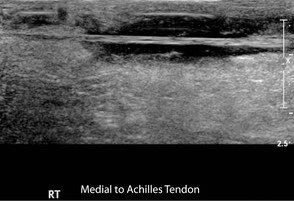

• Sagittal views (Figs. 8 and 9) and a panoramic view (Fig. 10) of the upper AT reveal a full-thickness tear located approximately 2–4 cm proximal to the calcaneal insertion. The gap between the torn edges (arrows) is filled with heterogeneous material and fluid, also noted on transverse view (Fig. 11). The smaller plantaris tendon remains intact on the medial side (arrow in Fig. 12).

• Pitfall: Confusing the medial plantaris tendon (Fig. 12) with residual intact AT fibers, which can mimic a partial tear.

• The plantaris tendon may remain intact even in complete AT rupture.

• Trace the plantaris tendon along its normal course between the gastrocnemius and soleus muscles.